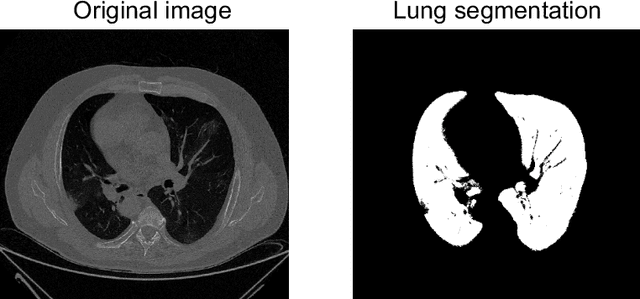

Abstract:The outbreak of the COVID-19 (Coronavirus disease 2019) pandemic has changed the world. According to the World Health Organization (WHO), there have been more than 100 million confirmed cases of COVID-19, including more than 2.4 million deaths. It is extremely important the early detection of the disease, and the use of medical imaging such as chest X-ray (CXR) and chest Computed Tomography (CCT) have proved to be an excellent solution. However, this process requires clinicians to do it within a manual and time-consuming task, which is not ideal when trying to speed up the diagnosis. In this work, we propose an ensemble classifier based on probabilistic Support Vector Machine (SVM) in order to identify pneumonia patterns while providing information about the reliability of the classification. Specifically, each CCT scan is divided into cubic patches and features contained in each one of them are extracted by applying kernel PCA. The use of base classifiers within an ensemble allows our system to identify the pneumonia patterns regardless of their size or location. Decisions of each individual patch are then combined into a global one according to the reliability of each individual classification: the lower the uncertainty, the higher the contribution. Performance is evaluated in a real scenario, yielding an accuracy of 97.86%. The large performance obtained and the simplicity of the system (use of deep learning in CCT images would result in a huge computational cost) evidence the applicability of our proposal in a real-world environment.

Abstract:The new coronavirus has caused more than 1 million deaths and continues to spread rapidly. This virus targets the lungs, causing respiratory distress which can be mild or severe. The X-ray or computed tomography (CT) images of lungs can reveal whether the patient is infected with COVID-19 or not. Many researchers are trying to improve COVID-19 detection using artificial intelligence. In this paper, relying on Generative Adversarial Networks (GAN), we propose a Semi-supervised Classification using Limited Labelled Data (SCLLD) for automated COVID-19 detection. Our motivation is to develop learning method which can cope with scenarios that preparing labelled data is time consuming or expensive. We further improved the detection accuracy of the proposed method by applying Sobel edge detection. The GAN discriminator output is a probability value which is used for classification in this work. The proposed system is trained using 10,000 CT scans collected from Omid hospital. Also, we validate our system using the public dataset. The proposed method is compared with other state of the art supervised methods such as Gaussian processes. To the best of our knowledge, this is the first time a COVID-19 semi-supervised detection method is presented. Our method is capable of learning from a mixture of limited labelled and unlabelled data where supervised learners fail due to lack of sufficient amount of labelled data. Our semi-supervised training method significantly outperforms the supervised training of Convolutional Neural Network (CNN) in case labelled training data is scarce. Our method has achieved an accuracy of 99.60%, sensitivity of 99.39%, and specificity of 99.80% where CNN (trained supervised) has achieved an accuracy of 69.87%, sensitivity of 94%, and specificity of 46.40%.